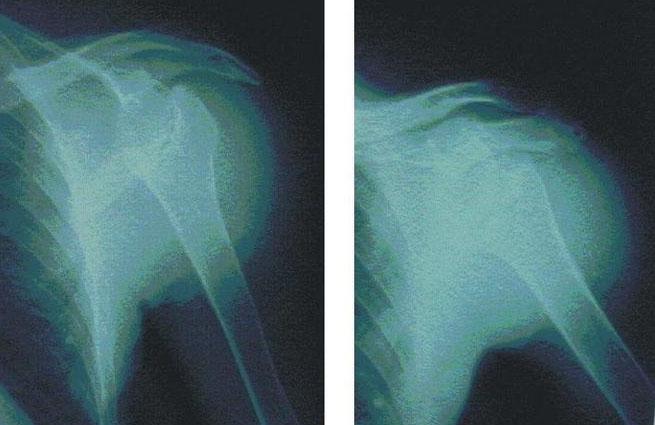

El hombro es una compleja articulación cuyas dos principales funciones son dar movilidad a los brazos y, al mismo tiempo, aportar estabilidad suficiente para facilitar su función. La luxación de hombro suele aparecer como consecuencia de un golpe, un encontronazo con otro jugador o una caída donde el peso recae sobre la mano o el codo y éstos están ligeramente separados.

Cuando el hueso (en este caso el húmero) se desplaza y vuelve a su posición natural de manera espontánea entonces hablamos de subluxación de hombro. Si la lesión se produce de manera frecuente, entonces se debe optar por la cirugía tradicional para subsanar el problema. Si por el contrario su aparición ha sido ocasional se debe optar por un tratamiento más conservador.